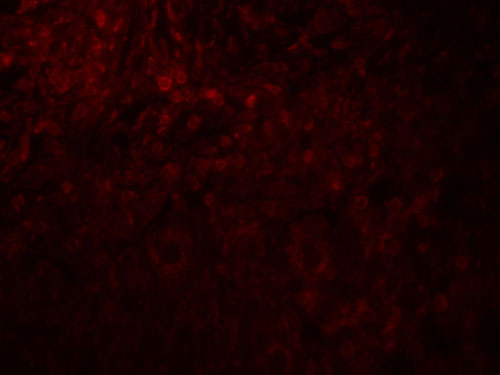

Images |

Western blot analysis of MAGEA4 in A431 cell lysate with MAGEA4 antibody at 1 μg/ml.

Immunofluorescence of MAGEA4 in human breast cancer tissue with MAGEA4 antibody at 20 μg/mL. |